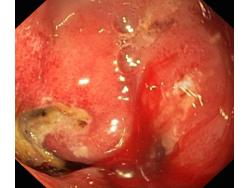

Wrzód trawienny